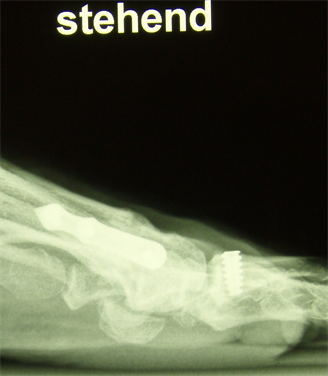

Figure 12. (a) Patient Nr. 3. Hallux valgus, pathologic DMAA; (b) Patient Nr. 3 Elevation of the Ist metatarsal of 3 mm.

Figure 15. Patient Nr. 3. The elevation of the I metatarsal was equalized by plantarization of the head of 3 mm.